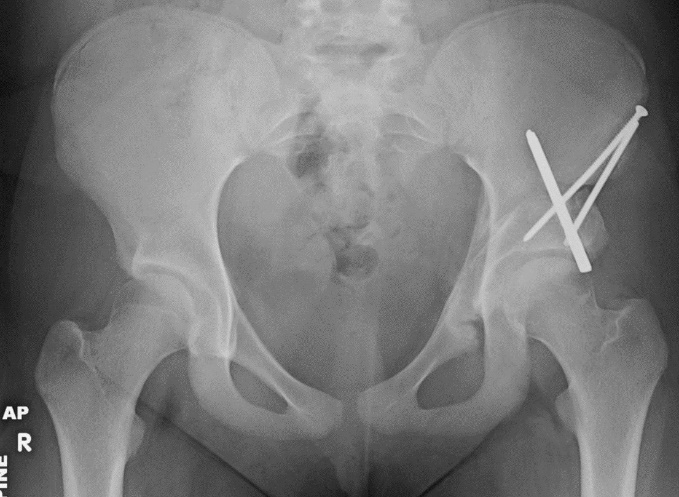

Triple osteotomy — radiograph

Triple osteotomy — radiograph.